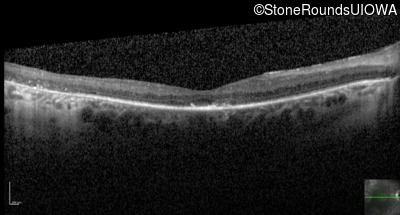

Optical Coherence Tomography - Left - 20/30 +2

Exemplar / OCT Stack

OCT Stack